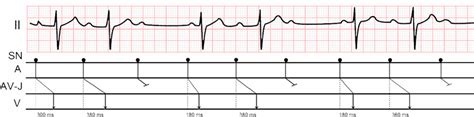

Let’s kick things off by really understanding what we’re dealing with here: Wenckebach second-degree AV block . This isn’t just some fancy medical term; it describes a specific electrical issue in the heart that, while often benign, absolutely requires proper identification. Imagine your heart as a well-oiled machine with an incredibly precise electrical system that dictates every beat. In a healthy heart, electrical signals start in the atria (the upper chambers), travel down through a special junction called the atrioventricular (AV) node, and then spread to the ventricles (the lower chambers), making them contract and pump blood. Now, in a Wenckebach second-degree AV block , also known as Mobitz Type I , something peculiar happens at that AV node. Instead of consistently relaying the signal from the atria to the ventricles in the same amount of time, the AV node starts to get a bit sluggish. Each consecutive electrical impulse from the atria takes longer to pass through the AV node than the one before it, until eventually, one impulse fails entirely to make it through to the ventricles. It’s like a train that keeps slowing down at each station until it misses one completely, and then the whole process resets. This results in a pattern where you see a progressively lengthening PR interval on an electrocardiogram (ECG), followed by a dropped QRS complex, and then the cycle repeats. Clinical presentation can vary widely, guys; some individuals with Wenckebach second-degree AV block might not even notice they have it, experiencing no symptoms at all. Others might feel a bit lightheaded, dizzy, fatigued, or experience palpitations because their heart rate isn’t as steady as it should be. Causes can range from increased vagal tone (often seen in athletes), certain medications (like beta-blockers or calcium channel blockers), electrolyte imbalances, or even underlying heart conditions. Diagnosing Wenckebach second-degree AV block primarily relies on a detailed ECG analysis, where healthcare professionals meticulously look for that characteristic progressive PR prolongation and the dropped beat. Understanding these clinical characteristics is paramount for accurate diagnosis and, by extension, for correctly applying the ICD-10 code for Wenckebach second-degree AV block . Without a solid grasp of what’s happening in the heart, coding becomes a shot in the dark, and that’s not what we want when it comes to patient care or financial accuracy. This deep understanding ensures that when you see documentation of Wenckebach , you instantly know what it signifies both clinically and for coding purposes, making your job much smoother and significantly more precise. So, remember, it’s all about that progressively sluggish AV node leading to a dropped beat, and then the cycle begins anew. That distinct pattern is the key identifier, and recognizing it is your first step towards correct coding.